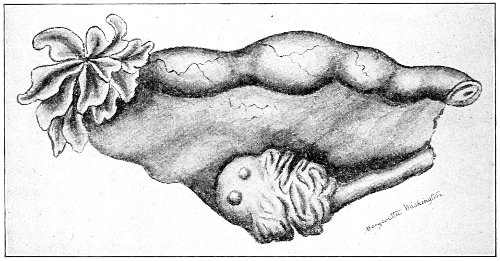

Gynecology is the study of diseases peculiar to women. As woman possesses organs which man has not, and as the parts—physiological and social—that she plays in life differ from those played by man, we should expect to find her afflicted with a certain number of diseases, peculiar to her, which are dependent upon her anatomy, physiology, and mode of life. Such diseases occur in barbarous as well as in civilized women; and similar diseases, peculiar to the female, occur in the lower animals. Thus, in the cow and the mare we find tumors of the vagina, prolapse of the vagina and uterus, fibroid tumors, sarcoma and cancer of the uterus, and some forms of ovarian cysts. Cysts of the tubes and the ovaries are exceedingly common in old mares; cats and goats are similarly affected.

Fibroid tumors of the uterus, which are so common among the colored women of this country, are said by Tait to be unknown among their African cousins, who are removed by but a few generations.

Celibacy is an unnatural state and a common cause of disease. Certain forms of fibroid tumors of the uterus are more common in single than in married women, and more common in sterile than in childbearing women. And the painful cirrhotic ovaries of the old maid are the result of the unceasing menstrual congestions never relieved by pregnancy and lactation. 19